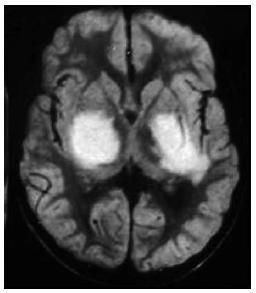

El hipocampo es una estructura crítica para procesar y recordar información espacial y contextual. En base a esta premisa, se pretende evaluar el papel de esta estructura del lóbulo temporal medial en una tarea de aprendizaje espacial: el laberinto acuático de Morris. El laberinto de agua fue diseñado en 1984 por Richard G. Morris para estudiar y evaluar el aprendizaje y la memoria espacial en ratas de laboratorio. El laberinto acuático es una piscina circular llena de agua a una temperatura que oscila entre los 18 y los 27° C, según se utilicen ratas o ratones, en la que se sumerge una plataforma que debe ser localizada por el animal. El agua se vuelve opaca con leche o alguna sustancia no tóxica como el látex para que el animal no vea la plataforma, aunque se ha demostrado que esto no es necesario, ya que el animal nada con la cabeza por encima del agua, lo que le impide ver la plataforma.

En la versión tradicional del laberinto, los sujetos experimentales nadan desde diferentes puntos de salida, situados en el perímetro de la piscina, hasta encontrar la plataforma escondida bajo el agua. Para localizar la plataforma, el sujeto depende de unos puntos de referencia, lo cual implica un amplio rango de posibilidades tales como pequeños objetos localizados inmediatamente alrededor de la circunferencia de la piscina.

Imagínese que se quiere llevar a cabo un experimento para evaluar si las lesiones bilaterales del hipocampo deterioran el aprendizaje espacial en ratas utilizando esta tarea. Para ello, se diseña un procedimiento con dos condiciones experimentales: (A) intervención quirúrgica sin lesión hipocampal, (B) lesión bilateral del hipocampo. En este tipo de diseño, no podemos utilizar una estrategia de comparación intrasujeto, ya que la manipulación de la VI hace que la condición experimental sea irreversible. Si se utiliza el contrabalanceo como técnica de aleatorización, únicamente podría llevarse a cabo el orden de presentación de los niveles de la VI AB, pero no el orden BA (ya que la lesión del hipocampo hace la situación irreversible). Para llevar a cabo este experimento, necesitaríamos utilizar una estrategia de comparación intersujeto y comparar grupos independientes. Si la muestra es suficientemente grande y se utiliza un procedimiento probadamente aleatorio para asignar los sujetos a las condiciones experimentales, podemos asumir que las variables extrañas se equilibrarán formando grupos equivalentes.

Figura 21. Ejemplo de contrabalanceo: estudio del hipocampo.